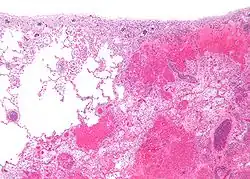

Infarto

Se denomina infarto a la necrosis coagulativa por una lesión isquémica de un órgano (muerte de un tejido por falta de sangre y posteriormente oxígeno), generalmente por obstrucción de las arterias que lo irrigan, ya sea por elementos dentro de la luz del vaso, por ejemplo placas de ateroma, o por elementos externos (tumores que comprimen el vaso, por torsión de un órgano, hernia de un órgano a través de un orificio natural o patológico, etc.). El infarto al miocardio se produce al taponarse una arteria que lleva la sangre al corazón. Los infartos pueden producirse en cualquier órgano o músculo, pero los más frecuentes se presentan: